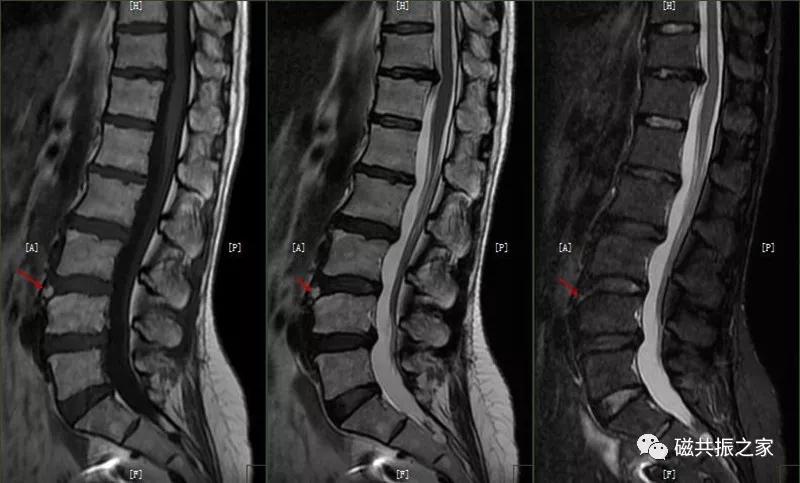

7.腰椎椎体滑脱

脊椎滑脱是指椎体相对下一节椎体向前或后方滑动移位,颈椎、腰椎常见。腰椎以4/5椎体和腰/骶连接部常见。滑脱分为向前和向后滑脱,根据上下椎体的滑动距离分为四度(在矢状位上将椎体上缘分为4等分,对应着1-4度滑脱)。